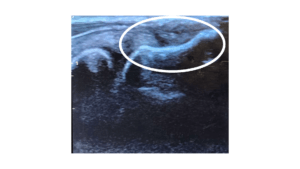

Lateral epicondylar (tennis elbow) tendon before and 12 weeks after PRP.

Notice the dark area (the tear) has filled in with new tendon.